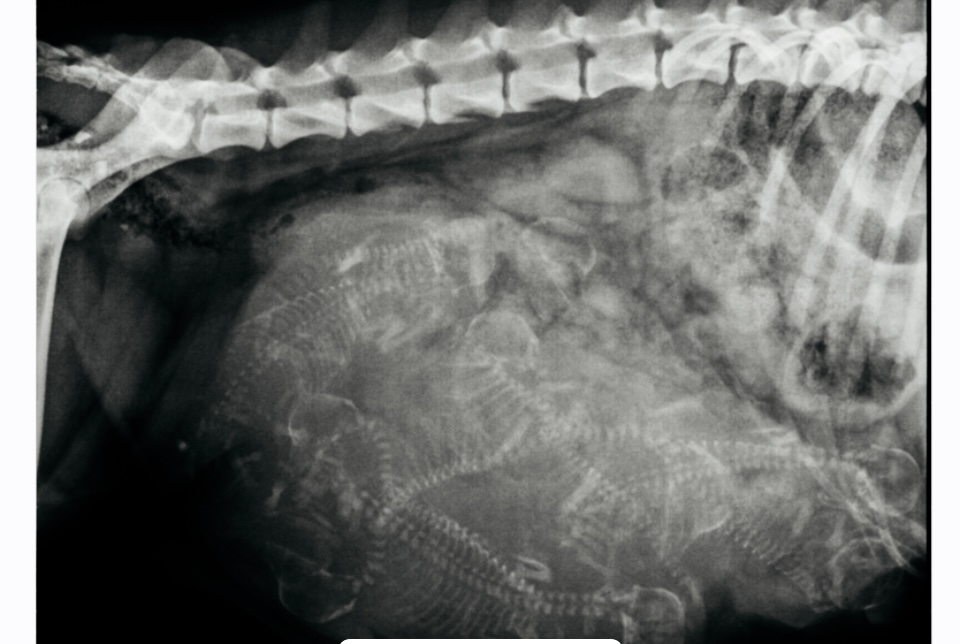

Tag 56: Ein paar Tage noch, dann wissen wir was Luigi und Summer produziert haben. Aktuell könnten es auch Schildkröten geben.Summer ist noch sehr entspannt.